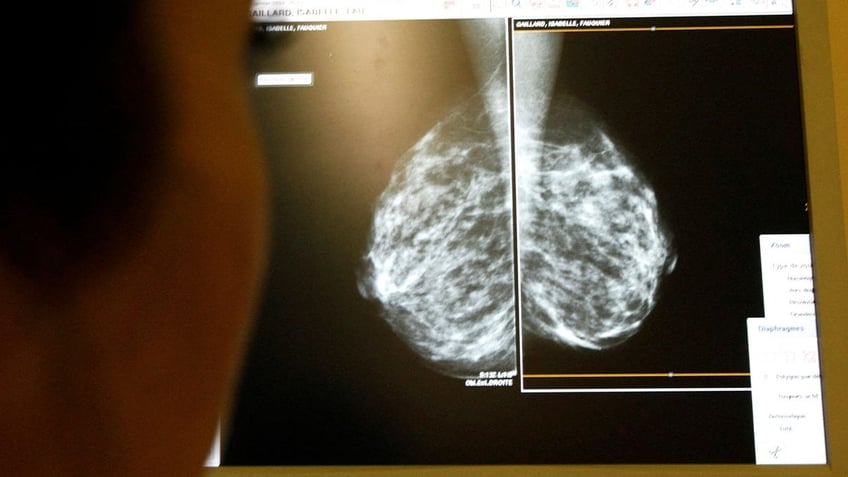

FILE: A doctor exams mammograms, a special type of X-ray of the breasts, which is used to detect tumors as part of a regular cancer prevention medical check-up at a clinic in France. (REUTERS/Eric Gaillard)